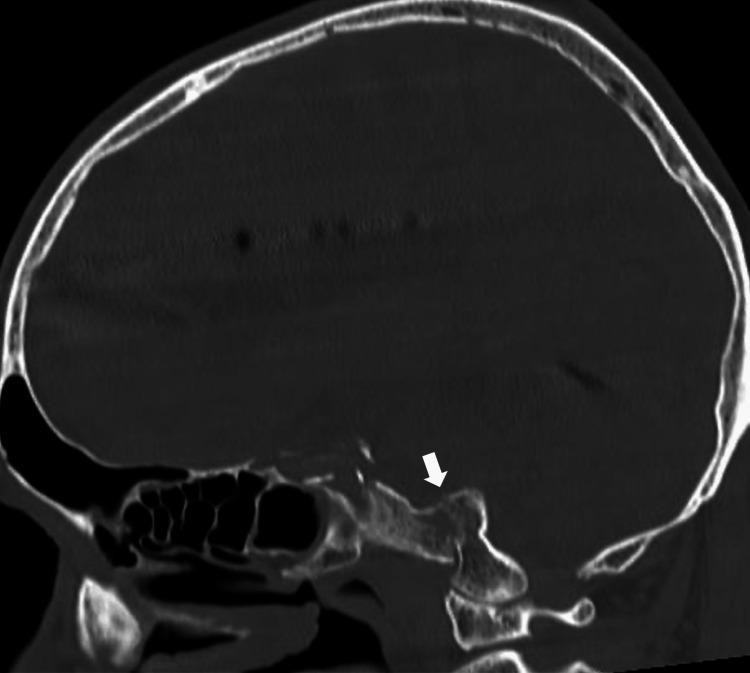

We present a rare case of clival fracture in which the patient presented with multiple lower cranial nerve palsy (similar to Vernet syndrome or Collet-Sicard syndrome). Multiple lower cranial nerve palsy from skull base lesions includes Vernet syndrome and Collet-Sicard syndrome. Clival fracture is a rare condition, and the optimal treatment method has yet to be established. A 73-year-old man fell down a flight of stairs and was diagnosed with injuries such as traumatic intracranial hemorrhage, clival fracture, and facial bone fracture. The patient presented with bilateral cranial nerve VI, IX, X, XI, and right XII palsies caused by clival fracture but no instability at the craniocervical junction, so we performed external fixation using a halo device. The patient developed delirium in the subacute phase, which was considered to be aggravated by the halo device. We therefore safely removed the halo device on hospital day 54 after confirming porosis of the fractured clivus on computed tomography. The patient did not complain of neck pain, and paralyses of cranial nerves VI and XII had completely resolved, while those of cranial nerves IX, X, and XI had also improved, so the patient could start direct swallowing training. Clival fracture with bilateral multiple cranial nerve palsies similar to Vernet syndrome or Collet-Sicard syndrome is highly rare. Accordingly, no standard treatment has been established. A halo device can be an effective treatment for clival fracture, and the duration of fixation could be determined flexibly based on the condition of each case.

摘要

我们报告一例罕见的斜坡骨折病例,该患者表现为多发性低位颅神经麻痹(类似于韦尔内综合征或科莱-西卡尔综合征)。由颅底病变引起的多发性低位颅神经麻痹包括韦尔内综合征和科莱-西卡尔综合征。斜坡骨折是一种罕见疾病,最佳治疗方法尚未确定。一名73岁男性从一段楼梯上摔倒,被诊断为创伤性颅内出血、斜坡骨折和面部骨折等损伤。该患者因斜坡骨折出现双侧颅神经VI、IX、X、XI及右侧XII麻痹,但颅颈交界处无不稳定情况,因此我们使用头环装置进行了外固定。患者在亚急性期出现谵妄,认为是头环装置加重了病情。因此,在计算机断层扫描确认骨折斜坡骨质疏松后,我们于住院第54天安全拆除了头环装置。患者未诉颈部疼痛,颅神经VI和XII的麻痹已完全缓解,而颅神经IX、X和XI的麻痹也有所改善,因此患者可以开始直接吞咽训练。类似于韦尔内综合征或科莱-西卡尔综合征的双侧多发性颅神经麻痹的斜坡骨折极为罕见。因此,尚未确立标准治疗方法。头环装置可为斜坡骨折提供有效治疗,固定时间可根据具体情况灵活确定。